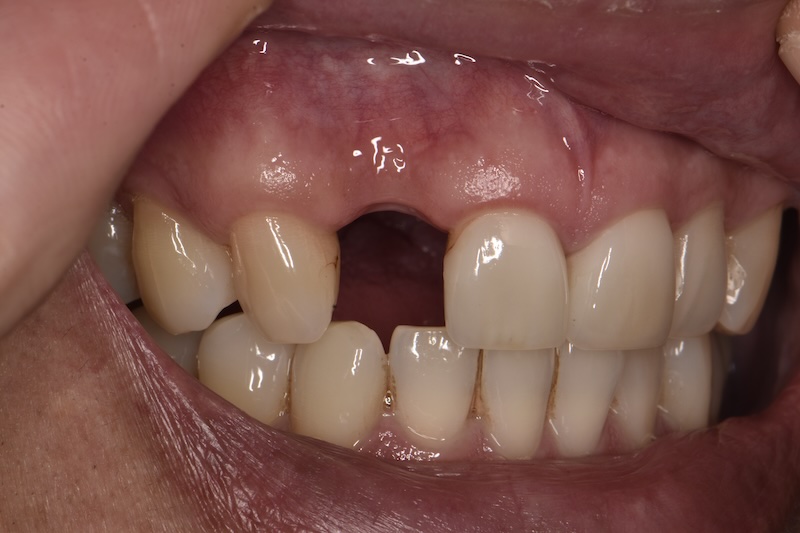

Foundation assessment

When a tooth has been missing for months or years, bone and gum tissue recede.

We rebuild the foundation first — grafting bone and tissue so the implant can be positioned where it should be, not just where there's room.

Immediate implantation

Planning an implant? If the tooth is still there — even if it's failing — how and when we remove it affects your outcome.

Same-day extraction and implant placement preserves the bone and gum tissue that would otherwise shrink while you wait.

For front teeth especially, this often means a more natural-looking result.